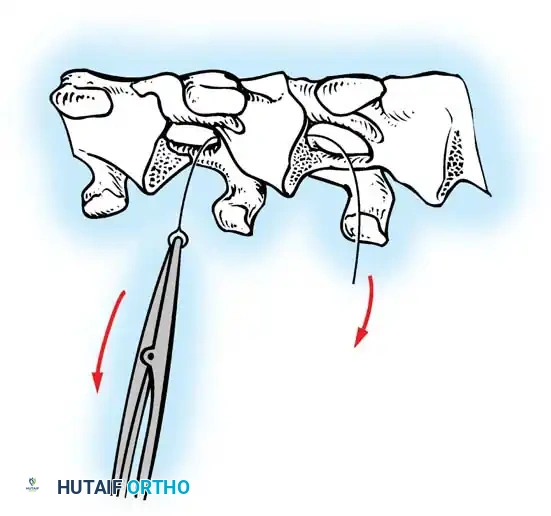

The Moe Technique (Thoracic Spine)

The Moe technique is a highly effective method for achieving intra-articular arthrodesis in the coronally oriented thoracic facet joints.

Fig. 38-26: The Moe technique of thoracic facet fusion, demonstrating the creation of hinged bone flaps.

- Expose the spine fully to the tips of the transverse processes.

- Using a sharp osteotome or Cobb gouge, begin a cut over the cephalad articular process at the base of the lamina.

- Carry this cut along the transverse process almost to its tip. Bend this cortical fragment laterally so it lies between the transverse processes, ideally leaving it hinged on its lateral periosteal attachment to preserve local vascularity.

- Thoroughly denude all articular cartilage from the superior articular process using a sharp curet.

- Make a secondary cut in the superior articular facet, working medially to laterally, producing another hinged fragment.

- Pack the resulting intra-articular defect tightly with cancellous bone graft.